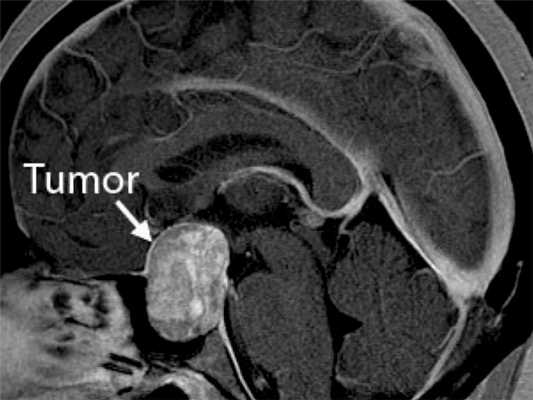

МРТ признаки доброкачественной мезенхимальной опухоли головы

Менингиомы

Растут не из тканей мозга, а из покрывающих его мягких оболочек (meninx),в связи с чем и получили свое название. Составляют около трети всех первичных новообразований. Наиболее часто наблюдаются у женщин, начиная со среднего возраста (в 2 раза чаще, чем у мужчин). Частота заболеваемости увеличивается после 60-ти лет. У детей встречаются редко. Типичное местоположение – в верхних отделах, но также могут образовываться у основания черепа. Обычно растут внутрь, вызывая сдавливание прилегающих отделов мозга. Иногда растут наружу, что сопровождается утолщением черепных костей в проблемной области. Могут содержать кальцинаты, заполненные жидкостью полости (кисты), сосудистые узлы.